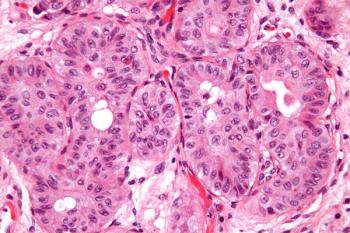

During Morning Rounds, Petros Grivas, MD, and his treating team debate the diagnosis of a patient with urothelial carcinoma as it has an unusual presentation.